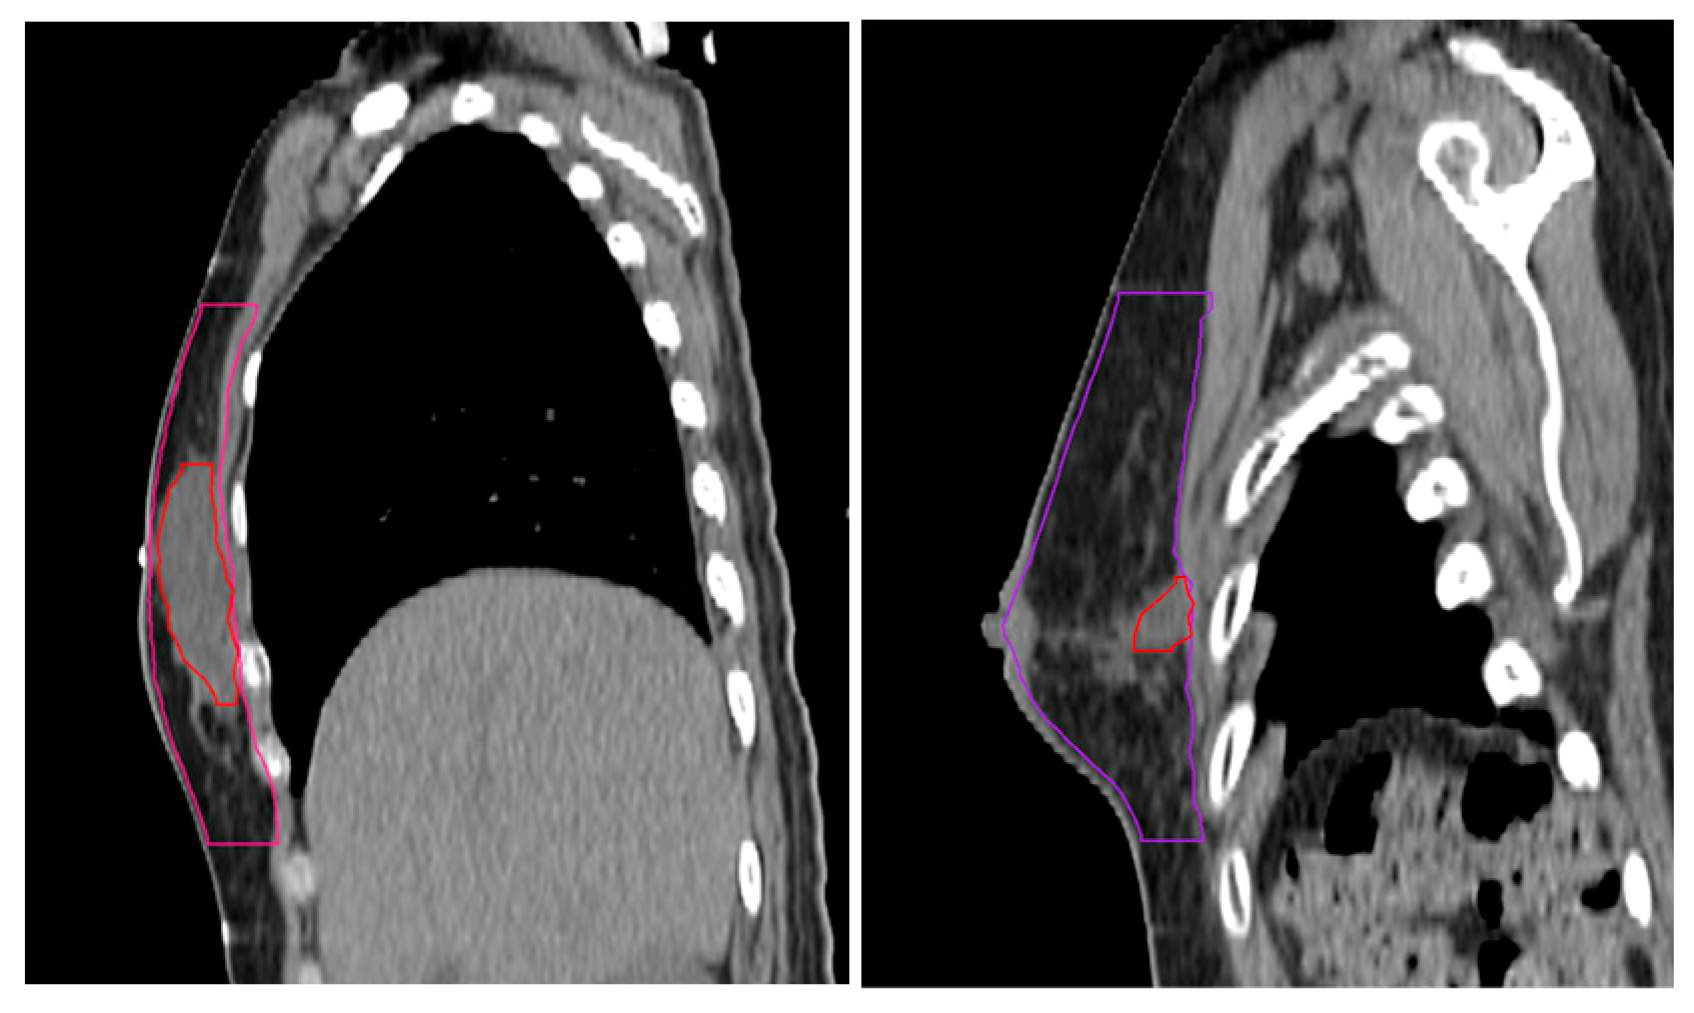

A single radiation oncologist specializing in breast cancer uniformly segmented the volumes (YHL). The cavity-to-breast ratio (%) was calculated as follows (Figure 2):

Cavity-to-breast ratio (%) = (Surgical cavity volume (cc))/(Breast volume (cc)) × 100

Figure 2. Segmentation of whole breast and surgical cavity with large (left) and small (right) cavity-to-breast ratios.